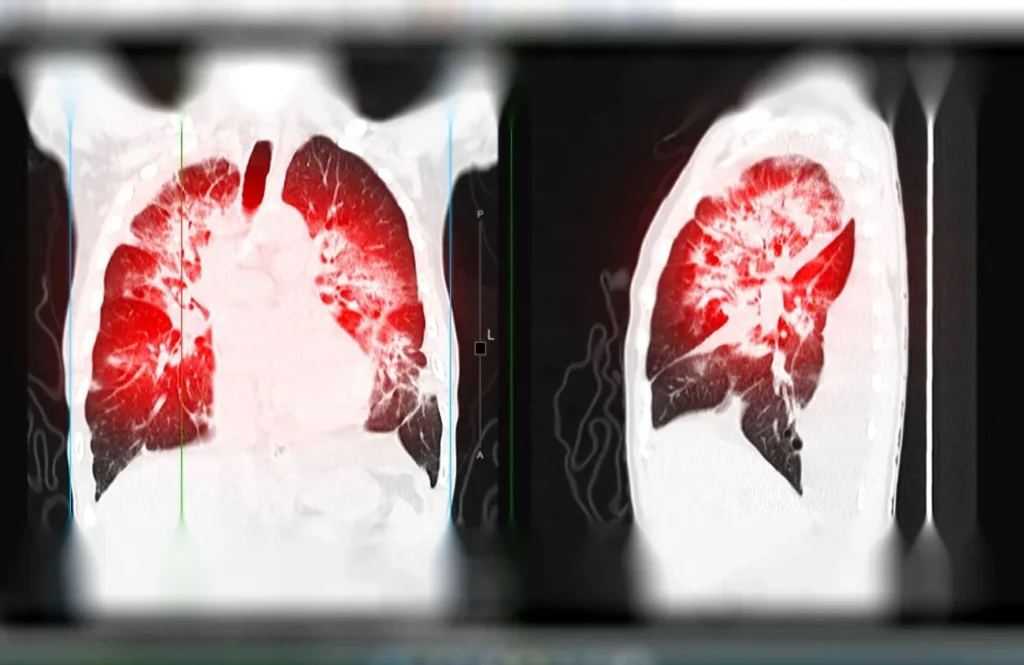

HRCT Chest in Navi Mumbai | Henotic Diagnostics

Need an HRCT Chest scan in Navi Mumbai? Henotic Diagnostics, Kharghar, offers advanced high-resolution CT imaging for accurate lung diagnosis. Our multi-slice HRCT detects ILD, fibrosis, bronchiectasis, tuberculosis, pneumonia, and COVID-related issues with clarity. Moreover, minimal radiation ensures safe scanning, while expert radiologists provide quick, precise reports. In addition, early detection aids effective treatment planning. Available in Kharghar, Panvel, Belapur, Nerul, Vashi, and Navi Mumbai, book your HRCT Chest scan today for expert lung care.